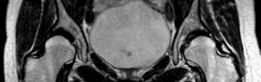

Advanced imaging with computed tomography (CT) with 3D reconstruction is increasingly utilized. 3D CT allows for precise mapping of the bony anatomy, evaluation of acetabular version, and virtual surgical planning. Magnetic resonance imaging (MRI) or MR arthrography is routinely obtained to evaluate the integrity of the labrum, articular cartilage, and ligamentum teres. Concomitant intra-articular pathology is highly prevalent in dysplastic hips and must be factored into the surgical plan, often necessitating a combined approach with hip arthroscopy or open arthrotomy.